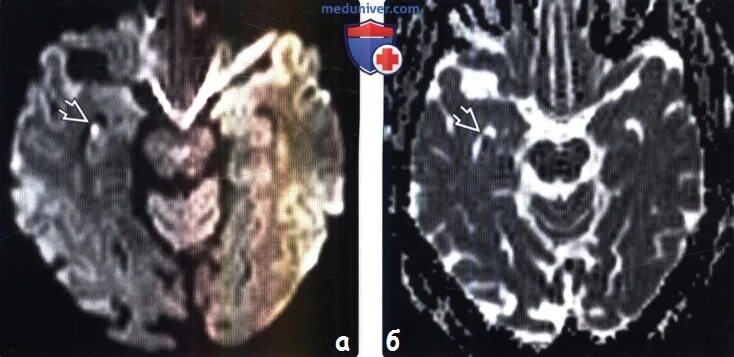

Очаг ограничения диффузии